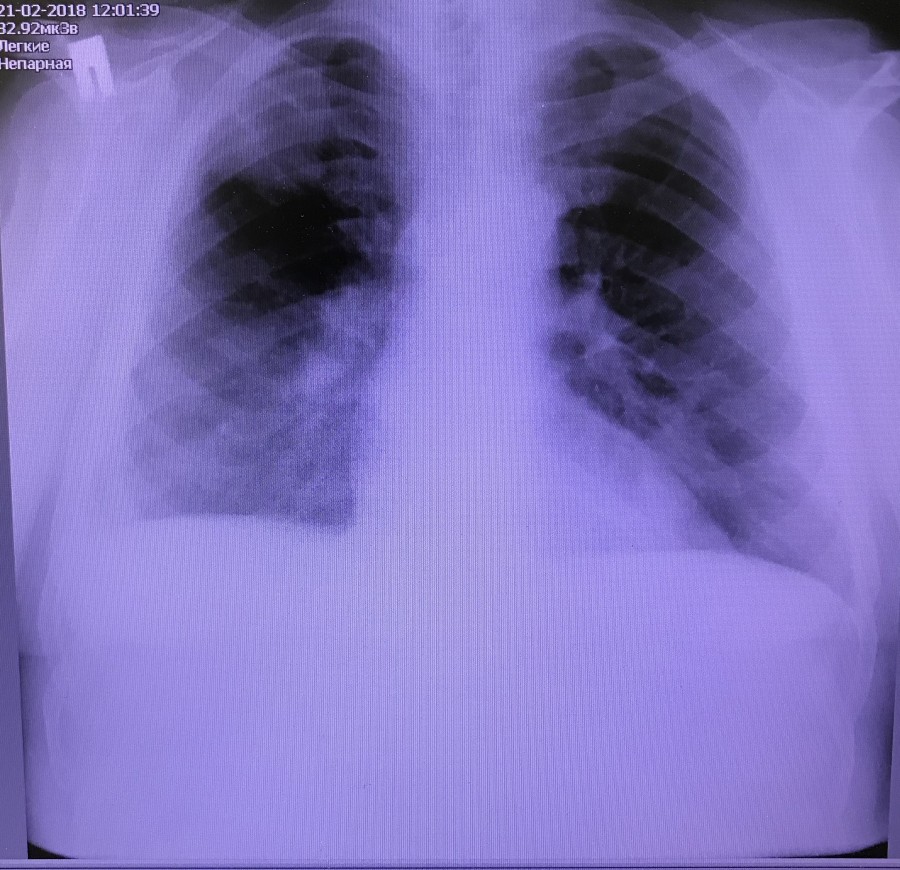

Заголовок сообщения: Периферическое образование

Обсуждалось здесь https://vk.com/club84409679?w=wall-84409679_7933%2Fall

2.jpg

2.jpg [ 189.9 KiB | Просмотров: 33041 ]